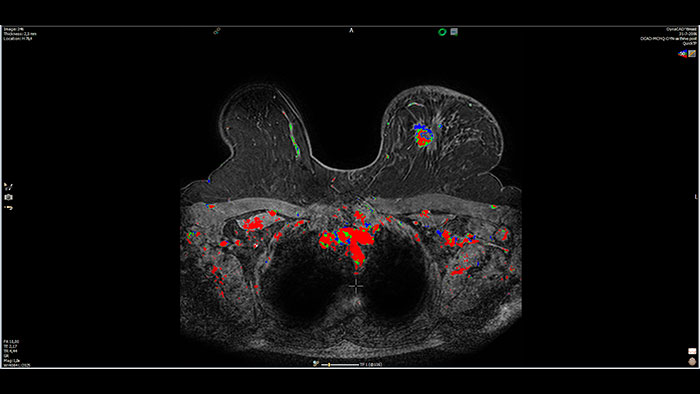

Next generation of breast care

Tailored to enhance the review and analysis of MRI breast studies by providing a flexible workspace with custom hanging protocols and multi-vendor** viewing capabilities. DynaCAD’s automatic segmentation allows on-the-fly user modification and provides volume analysis, lesion composition statistics, histograms, and a 3D rendered morphological overview.